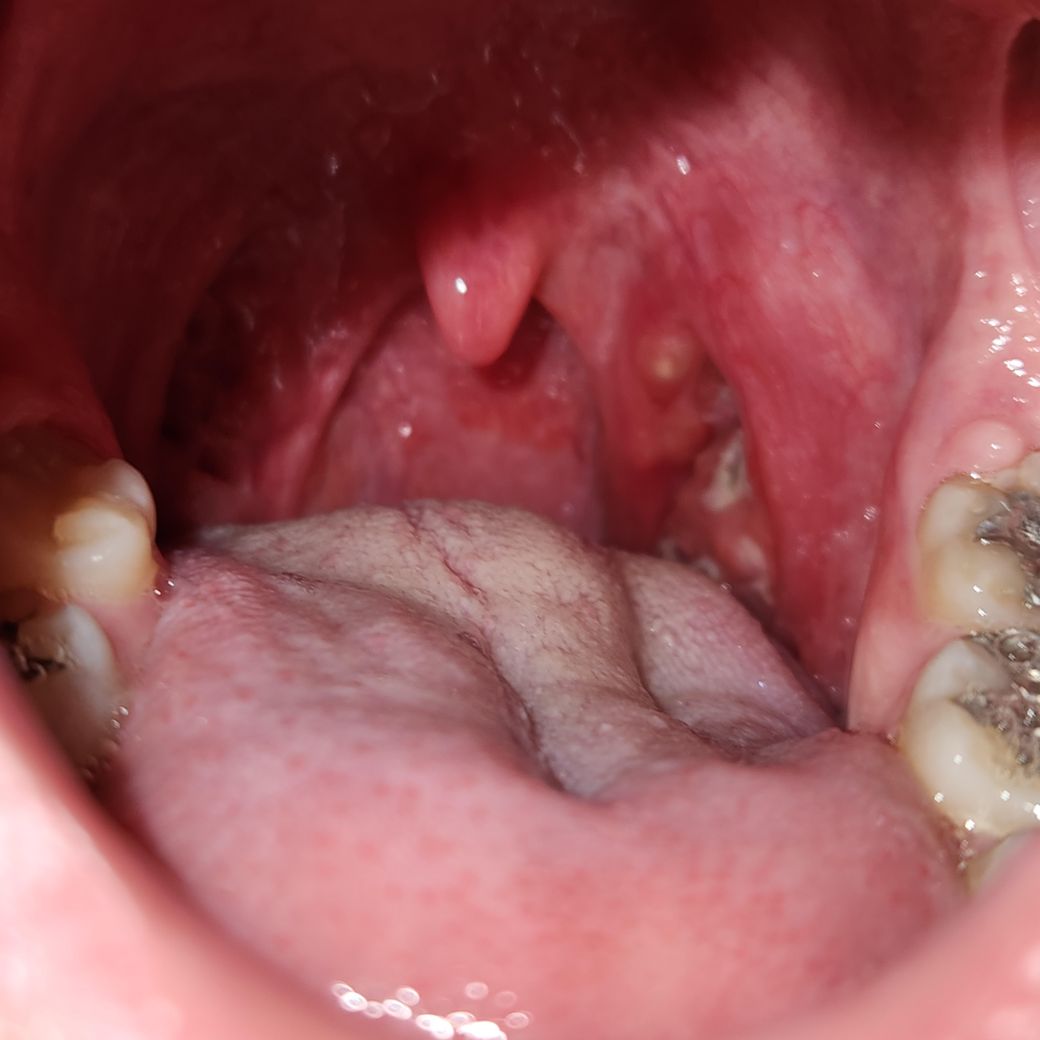

편도염인데 소렉신 연조엑스랑 병원에서 처방받은 약 같이 먹어도 될까요? 아니면 소렉신+타이레놀 따로 병원약만 먹는 게 좋을까요? 만약 그래야

편도염인데 소렉신 연조엑스랑 병원에서 처방받은 약 같이 먹어도 될까요?

아니면 소렉신+타이레놀 따로

병원약만 먹는 게 좋을까요?

만약 그래야 한다면 어느쪽이 더 낫나요?